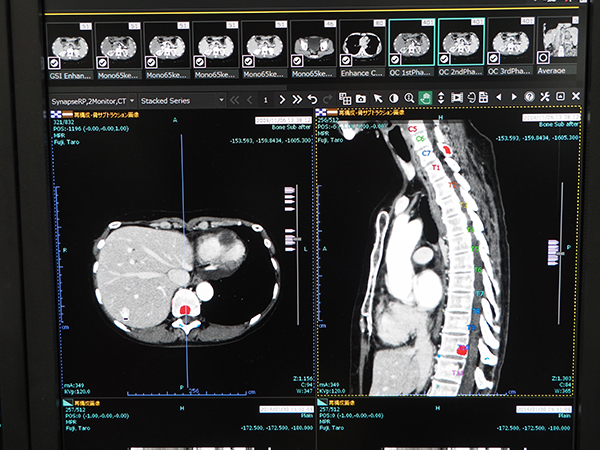

2) 骨経時サブトラクション

骨経時サブトラクションは,椎骨一つ一つを認識した上で過去画像との位置合わせを行い,CT値によるサブトラクションを行い経時的変化を算出して変化のある部分を色づけして表示する。圧迫骨折などで骨がなくなっていたりする場合でも,個々の椎骨を認識して正確に差分することが可能。読影時の経過や転移の観察は負荷が大きいが,自動認識によってサポートする機能だ。

SYNAPSE SAI viewerの“骨経時サブトラクション機能”